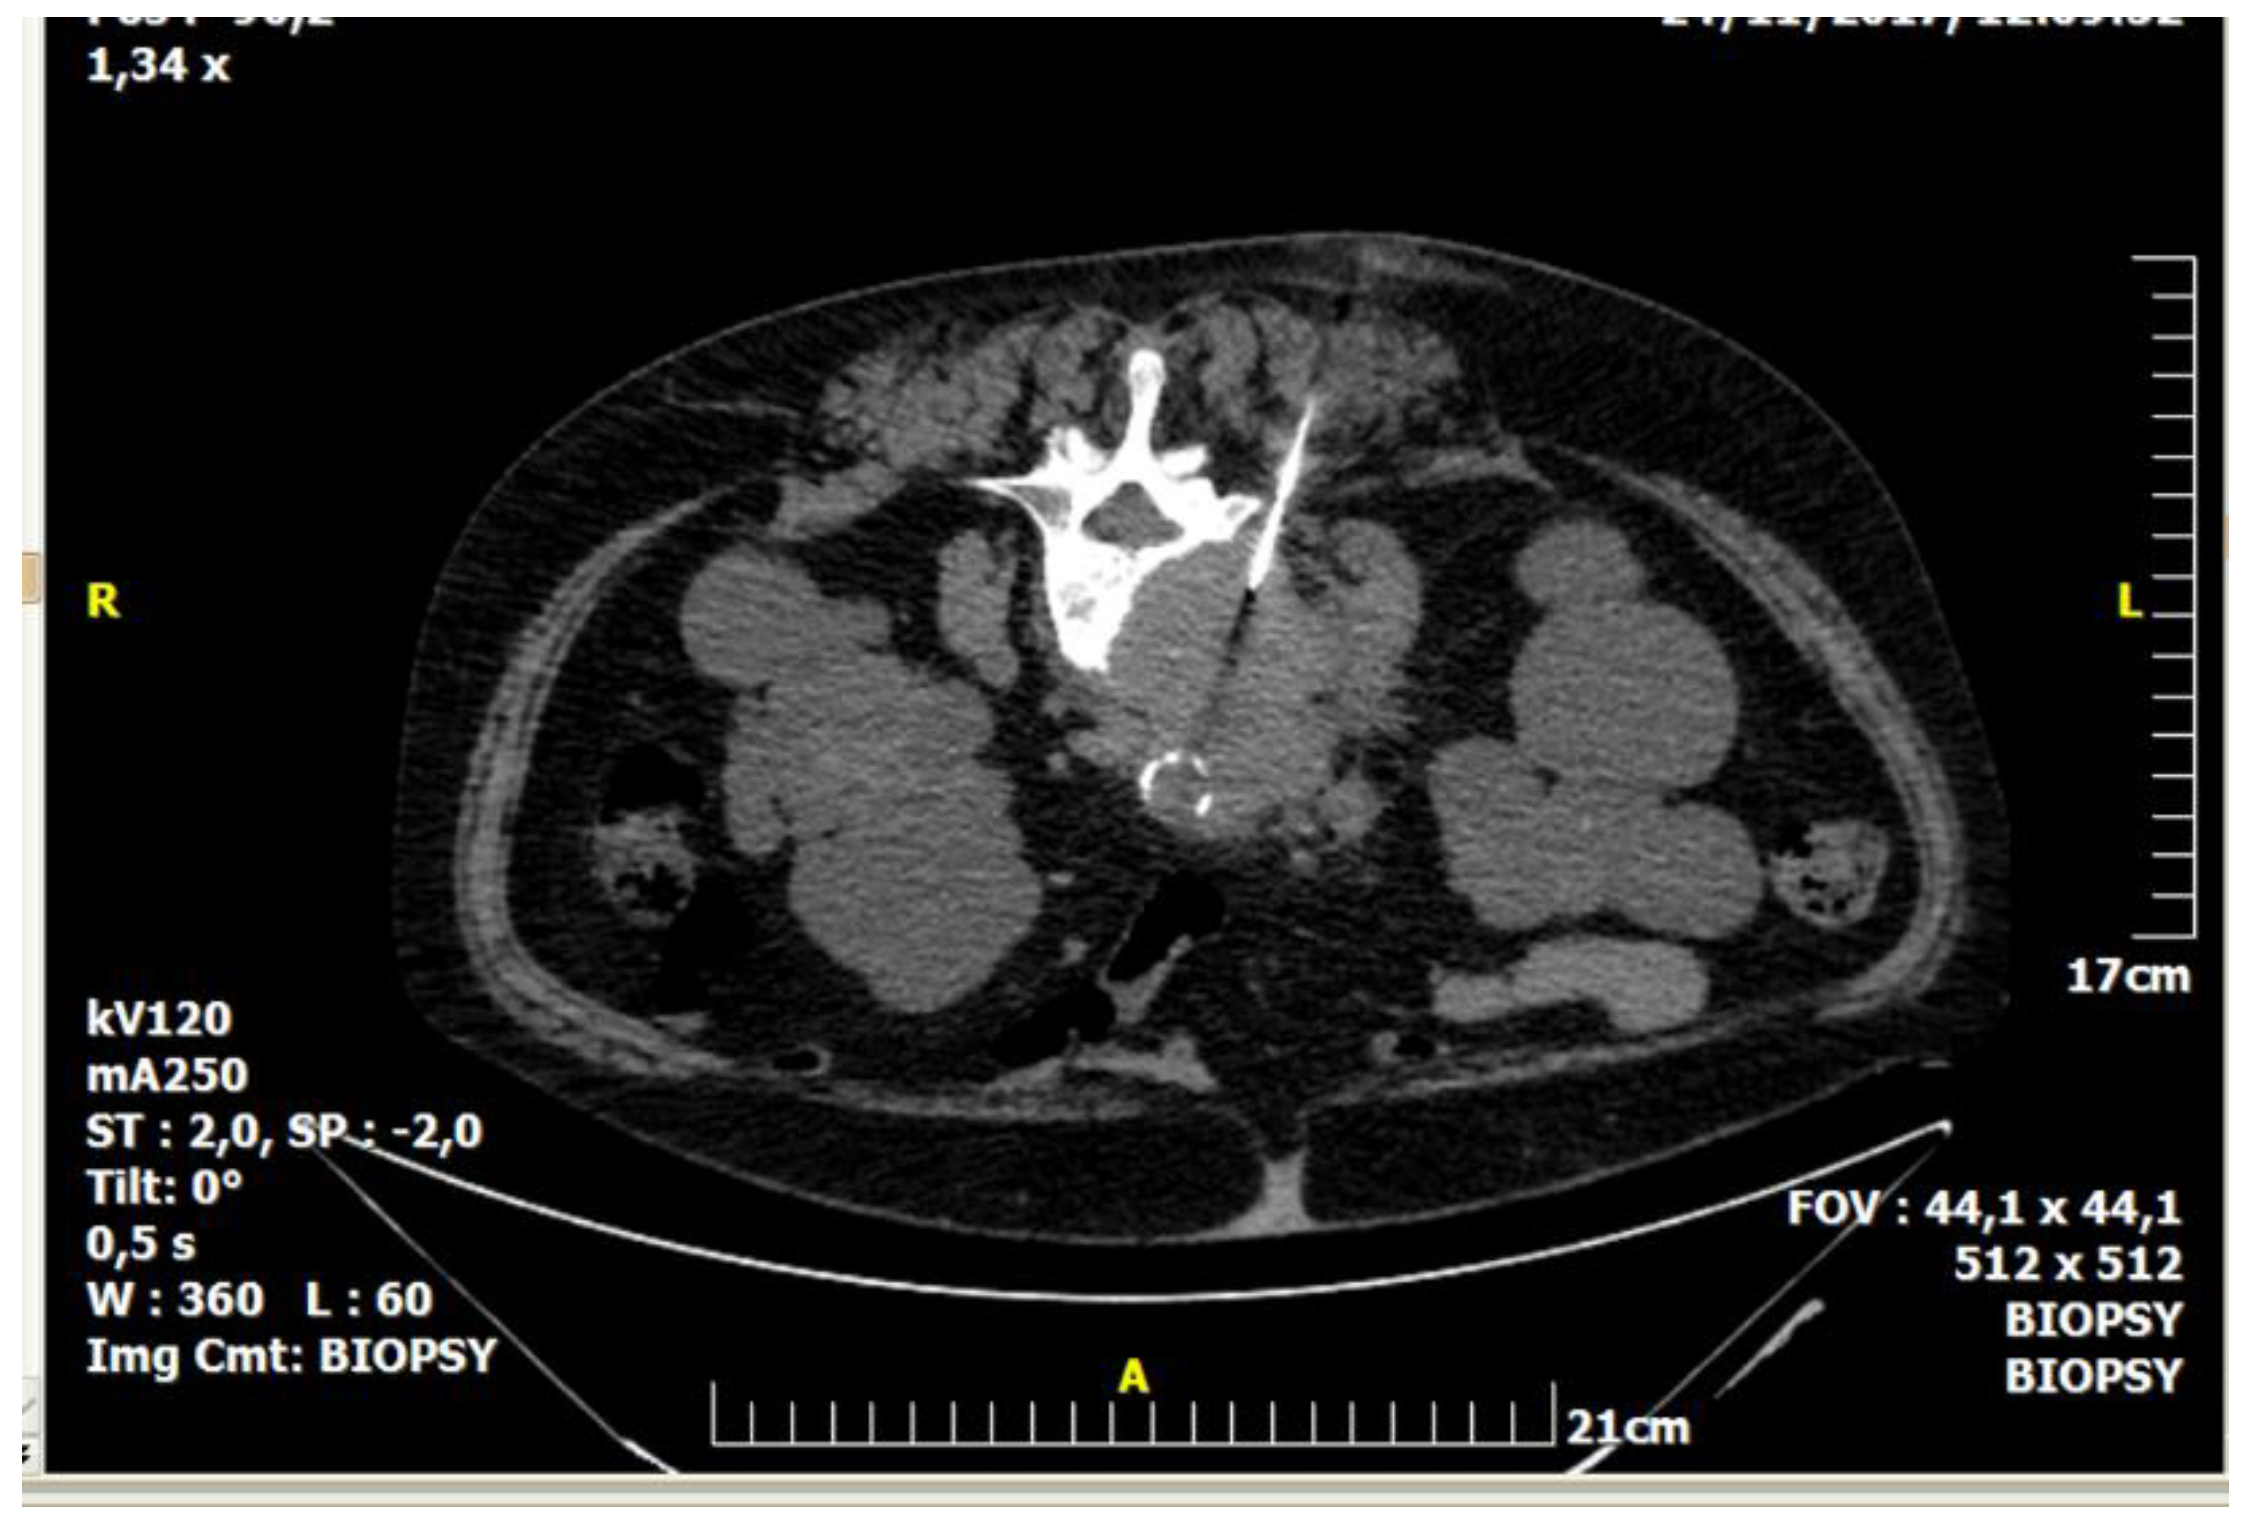

Figure 2.

A 64-year-old male patient with multiple osteolytic lesions. Computed tomography axial scan: there is a lytic lesion in the right iliac bone. The result of percutaneous, imaging-guided biopsy was metastasis from small cell bronchogenic carcinoma.